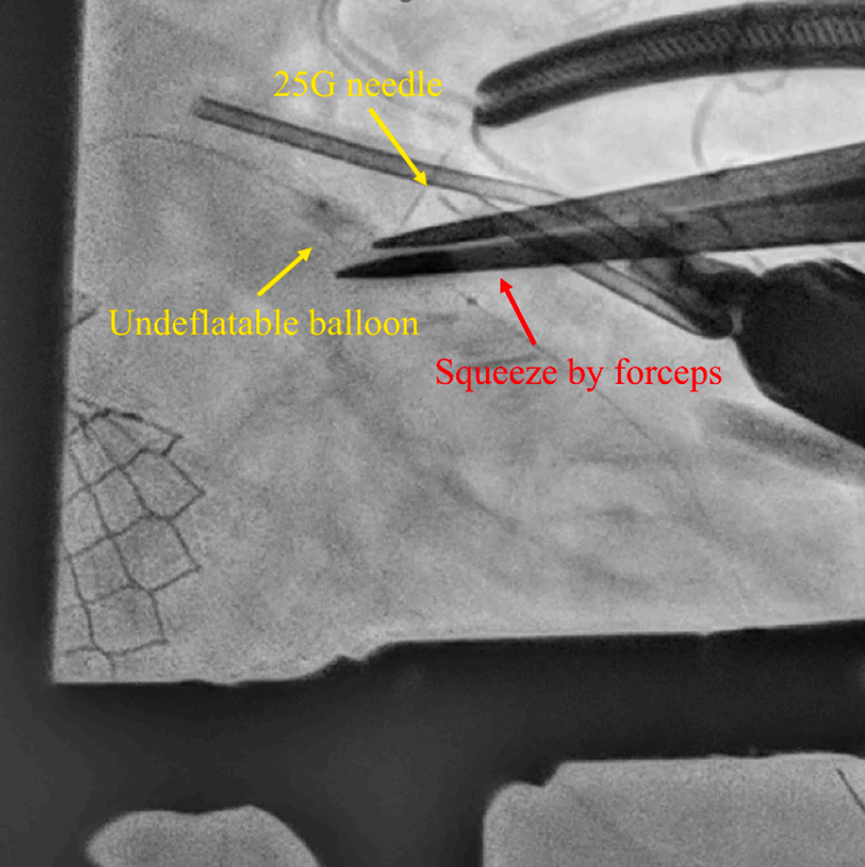

连续多次穿刺后球囊仍未排空,遂改用血管钳夹住球囊所在的冠脉段反复轻压,从冠脉外部协助将球囊内的造影剂挤出(图3)。从球囊卡滞到成功排空的总时间为194分钟。随后通过原有指引导管系统将瘪掉的球囊顺利拉出体外。

图3